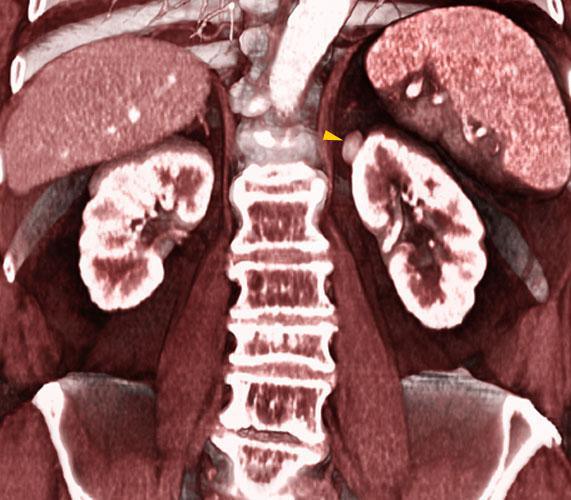

El TC (simple y contrastado) y la RM La diferenciación radiológica precisa un estudio de su localización, tamaño, densidades intratumorales, extensión, comportamiento con el contraste, afectación vascular y existencia de adenopatías locorregionales asi como afectación suprarrenal o metastásica.

Es indispensable una aproximacion prequirúrgica que determine la vascularización arterial y venosa de los riñones